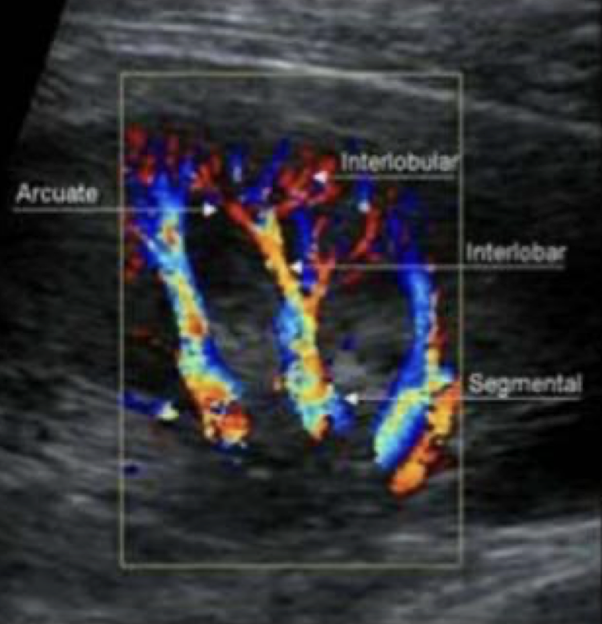

renal vasculature

M.S.I.A.I.

main renal artery

segmental renal artery

at hilum

interlobar arteries

between/along pyramids

arcuate arteries

at base of pyramids

interlobular arteries

near edge of cortex